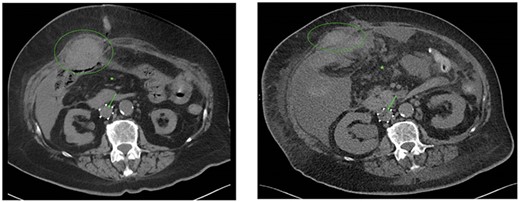

The patient was admitted to the emergency department 23 days after the oncoplastic breast surgery. She presented with abdominal pain, nausea, emesis and stool changes. General examination was normal and vital signs were normal except tachycardia. Abdominal distension, high-pitched tinkling bowel sounds and epigastric tenderness were observed. Laboratory tests revealed a white blood cell (WBC) count of 8.8*10E9/L and C-reactive protein (CRP) level of 19.4 mg/L. Abdominal computed tomography (CT) scan showed a short bowel obstruction caused by a stenosis in the terminal ileum and ileocecal junction without lymphadenopathy signs or metastasis. The basal lung segments were suspect for bilateral pulmonary embolisms (Fig. 2A–C), which was confirmed by a thoracic CT angiography. Retrospectively, an ileocecal tumor could not be identified on a follow-up PET/CT scan which was performed 7 weeks prior to emergency room presentation (Fig. 2D).

Coronal (A) and axial slice (B) of the abdominal CT scan at ER presentation showing small bowel obstruction with terminal ileum (green ellipse) and ileocecal junction stenosis. (C) CT scan at ER presentation also showed pulmonary embolisms in basal lung segments bilaterally (green ellipse). (2D) PET/CT performed 7 weeks prior to ER presentation showed no 18FDG uptake terminal ileum or ileocecal junction.